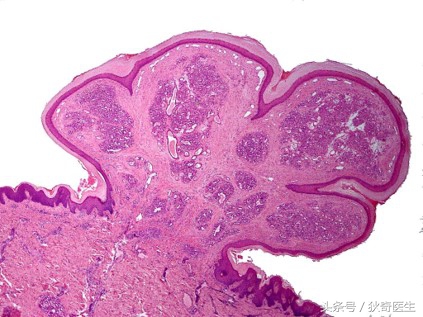

肉芽肿性血管瘤病理

肉芽肿性血管瘤又称化脓性肉芽肿,是发生于皮肤和黏膜面的一种息肉状血管瘤,为一种特殊类型的血管瘤。可发生于各年龄。发病原因不明,多认为与外伤、感染及激素水平等有关,其中与外伤关系密切,多为皮肤损伤后所形成新生血管形成的损害。好发于头面部、手足等。

1、外生型生长,紫红色,质脆,触碰易出血,出血较不易止。

2、反复出血其表面易出现溃疡,每次破溃后瘤体会较前增大,造成底部有蒂与皮肤或黏膜相连。